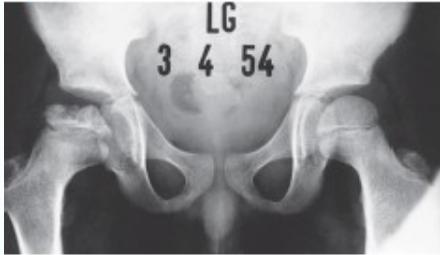

Radiographic Stages:

-

Initial/ Bone Death Stage - May initially appear normal on x-ray

- Increased density followed by collapse

Revascularization and Repair Stage - Reduced density and fragmentation on x-ray

Distortion and Remodeling Stage - Distortion, flattening (coxa plana)

- Enlargement (coxa magna) with partial uncoverage

Radiological Progression:

Progression: Sclerosis → Collapse → Fragmentation → Remodeling

Imaging Examples: